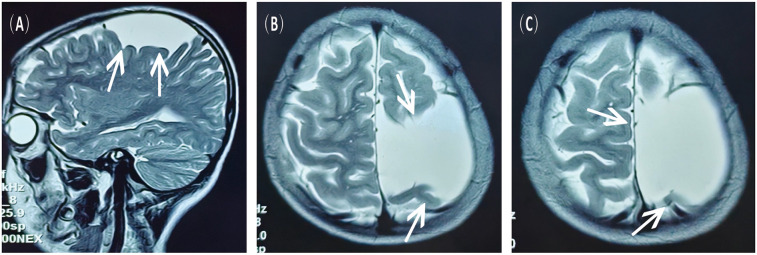

This case report discusses a 16-year-old male with a previously diagnosed left fronto-temporo-parietal arachnoid cyst (AC) who developed progressively worsening intermittent headaches. Magnetic resonance imaging (MRI) revealed a spontaneous chronic subdural hematoma (CSDH), despite no history of trauma or bleeding disorders. The cyst, discovered incidentally three years prior, had been asymptomatic until this event; hence, no interval cranial computed tomography (CT) or MR imaging was performed. The patient underwent burr-hole irrigation and drainage under general anaesthesia. Postoperative scans confirmed complete resolution of the hematoma and a significant reduction in the cyst size, with no recurrence of the cyst at the six-month follow-up. This case, supported by a systematic review of 28 recent studies (2020-2025), highlights that AC can spontaneously rupture, leading to CSDH. Burr-hole irrigation surgery proves to be a safe and efficient intervention, emphasizing the need for long-term monitoring in AC patients to manage potential hemorrhagic complications promptly.

Abstract Image